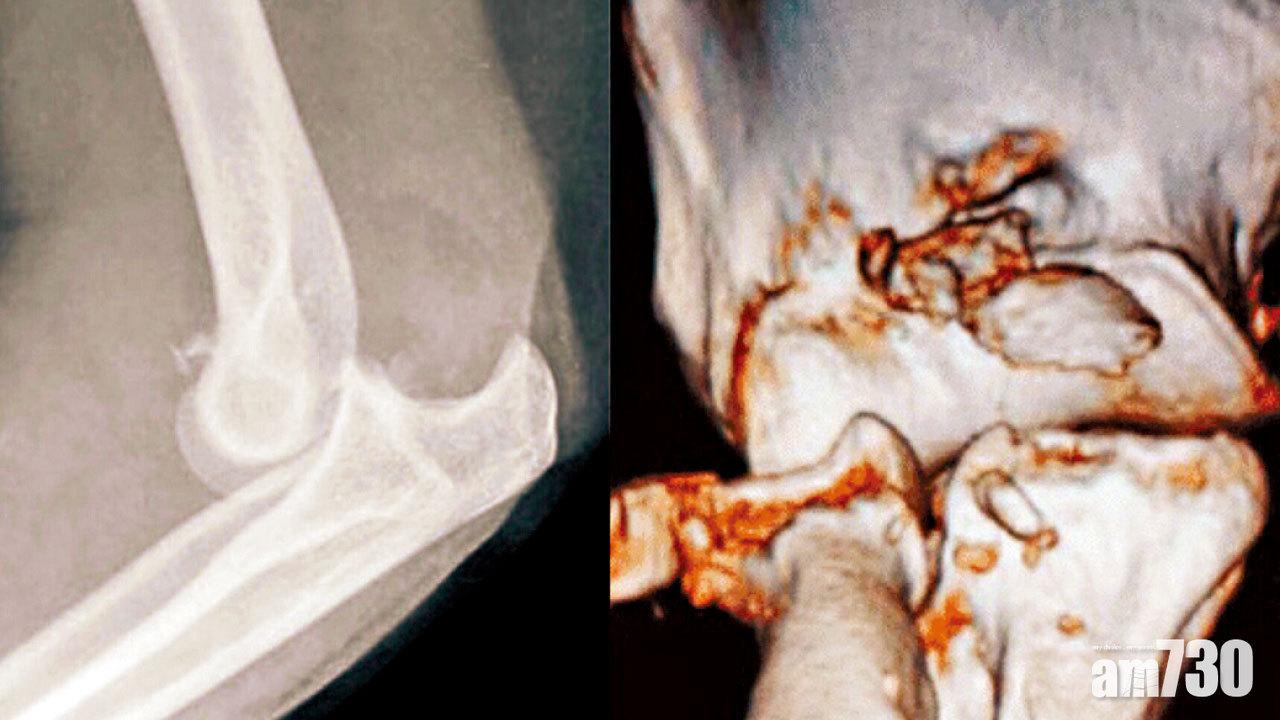

一旦發生手肘骨折及脫位,醫生會首先替病人復位並以石膏托固定。在術前安排照電腦掃描,加上三維影像重建,對評估骨折十分重要。手術主要以螺絲固定尺骨及橈骨骨折,修補副韌帶撕裂,並在肘關節仍不穩定下用外支架固定。萬一橈骨頭骨折屬粉碎性,將骨碎片移除,換上人工橈骨頭,通常都較內固定術更為可取。